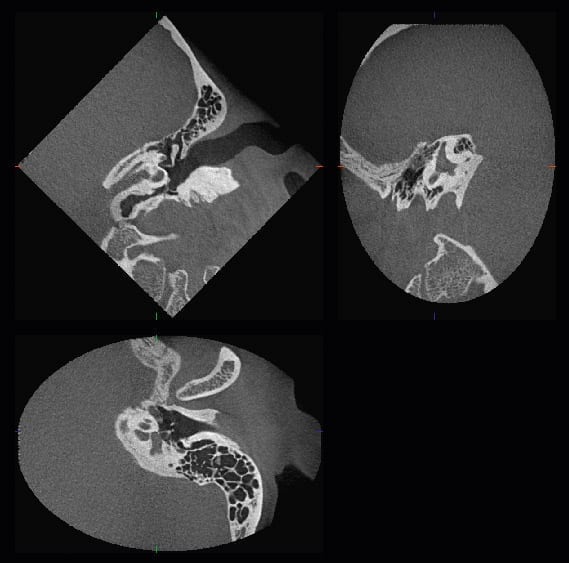

Zoom Reconstruction cho phép tạo ảnh độ phân giải cao từ dữ liệu gốc mà không cần chụp lại. Bác sĩ có thể phân tích vùng quan tâm ở voxel 80 µm ngay cả khi ban đầu chụp với FOV lớn — tiết kiệm thời gian và liều tia cho bệnh nhân.

- Nội nha: xác định ống tủy phụ, nứt gãy chân răng, tổn thương vùng chóp phức tạp

- Cấy ghép implant: đánh giá mật độ và thể tích xương hàm, vị trí ống thần kinh

- Chỉnh nha: phân tích 3D toàn hàm, răng ngầm, bất đối xứng xương

- Phẫu thuật miệng hàm mặt: lên kế hoạch cắt xương, u nang, u xương hàm

- Đánh giá TMJ: hình ảnh lồi cầu 3D, không gian khớp